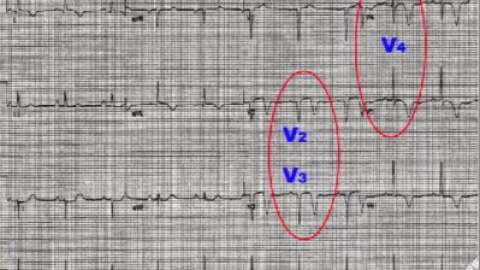

先天性长QT间期综合征是一种遗传性心脏离子通道病,而获得性长QT间期综合征代表由外在因素,通常是由药物或电解质异常导致离子通道功能的改变。因而成为“潜伏”的长QT间期综合征。长QT间期综合征的诊断主要...

QT间期延长综合征,指具有心电图上QT间期延长、室性心律失常、晕厥和猝死的一组综合征,可能伴有先天性耳聋。QT间期延长综合征,分原发性与继发性两种。女性、心律慢、低血钾都会增加继发性QT间期延长综合征...

com)9月16日消息-《柳叶刀》杂志报道心血管专业研讨会上关于先天性长/短QT综合征的最新资料。长QT间期综合征(LQTS)临床上一般按其病因分为遗传性和获得性,按其恶性心律失常发生机理又可分为长间...